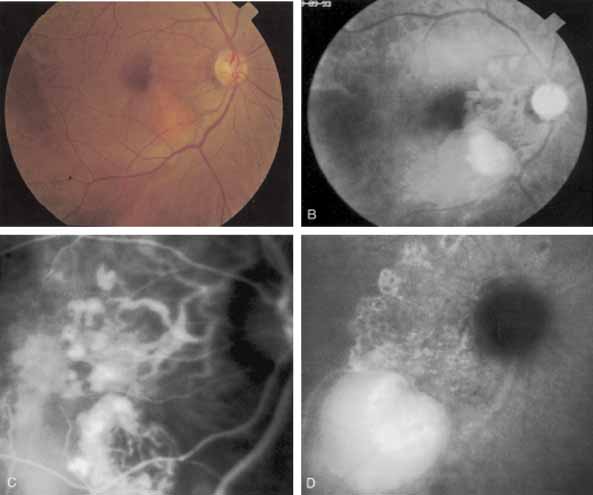

Harada disease, an inflammatory condition often affecting both eyes in young patients, is typified on fluorescein angiography by multiple focal areas of hypofluorescence early in the study, followed by late confluent leakage in the later phases (Fig. 17A, 17B, and 17C). With ICG angiography, multiple focal hypofluorescent spots are seen in the early phases, many more than were noted on the fluorescein study64,68 (Fig. 17D). The process extends further than the clinically or angiographically involved areas. The spots vary in size and density but appear to be well circumscribed. In the later phases of the ICG study, there is generalized hypofluorescence, with masking of the background choroidal fluorescence by the neurosensory detachment (Fig. 17E). This masking effect covers a large area, with inferior round margins confirming the gravitating nature of the neurosensory elevation. In addition, focal hyperfluorescent spots can be seen, possibly representing sites of active chorioretinal leakage or inflammation. In one patient, steroid therapy resulted in a marked resolution of clinical findings within 1 week.68 Repeat ICG angiography revealed a marked resolution of the hypofluorescent lesions as well as the hyperfluorescent spots. New areas of hypofluorescence did appear, the significance of which remains undetermined (Fig. 17E).

Fig. 17 Clinical photograph of a patient with Harada disease demonstrating multiple serous elevations of the retinal pigment epithelium with an overlying shallow neurosensory detachment. B. Early-phase fluorescein angiogram demonstrating hypofluorescent spots at the site of localized inflammation. C. Late-phase fluorescein study demonstrating hyperfluorescence in a confluent nature in the central macula. D. Early-phase indocyanine green (ICG) study demonstrating hypofluorescent spots in the central macular region. Note that the lesions are more numerous and more widely distributed than noted on clinical or fluorescein angiographic examination. E. Late-phase ICG study demonstrating extensive areas of confluent hypofluorescence. Note the curvilinear and gravitating nature of these hypofluorescent lesions, which are believed to represent blocked fluorescence from the shallow neurosensory detachment. Focal hyperfluorescent spots are noted within this region, which may represent areas of more active inflammation.